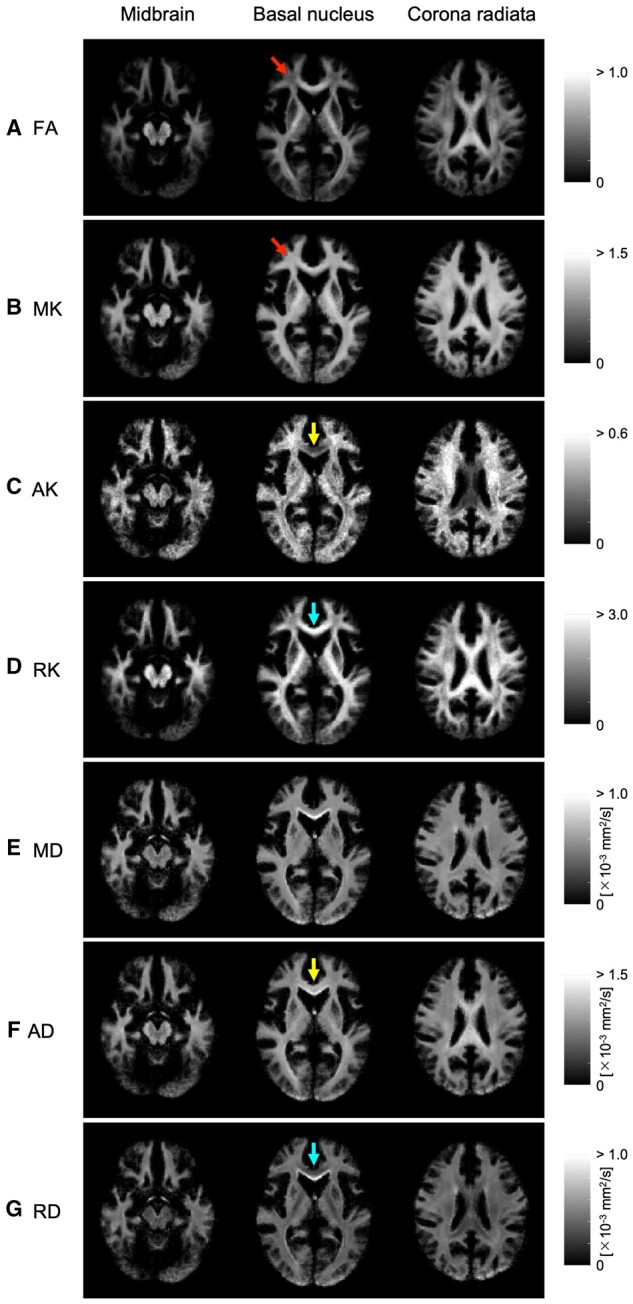

Results: The relationship between FA and kurtosis parameters (MK, RK, and AK) for WM areas had a strong positive correlation (FA-MK, R2 = 0.93; FA-RK, R2 = 0.89) and a strong negative correlation (FA-AK, R2 = 0.92). When comparing a TBSS connection, we found that this could be observed more clearly in MK than in RK and FA.

Abstract Image